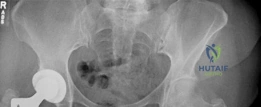

- The Concept of "Spot Welds": Over the first 6 to 12 months postoperatively, successful osteointegration of an extensively porous-coated stem can be visualized radiographically by the formation of "spot welds"—areas of dense endosteal bone bridging directly to the porous coating, typically seen at the distal extent of the porous coating.

This follow-up radiograph demonstrates the classic appearance of an extensively porous-coated stem that has achieved biologic fixation. Notice the absence of radiolucent lines around the diaphyseal portion of the stem, indicating a lack of fibrous tissue interposition.

A closer, magnified view of the distal stem highlights the subtle endosteal condensation and "spot weld" formation at the transition zone of the porous coating, confirming rigid, long-term biologic integration.